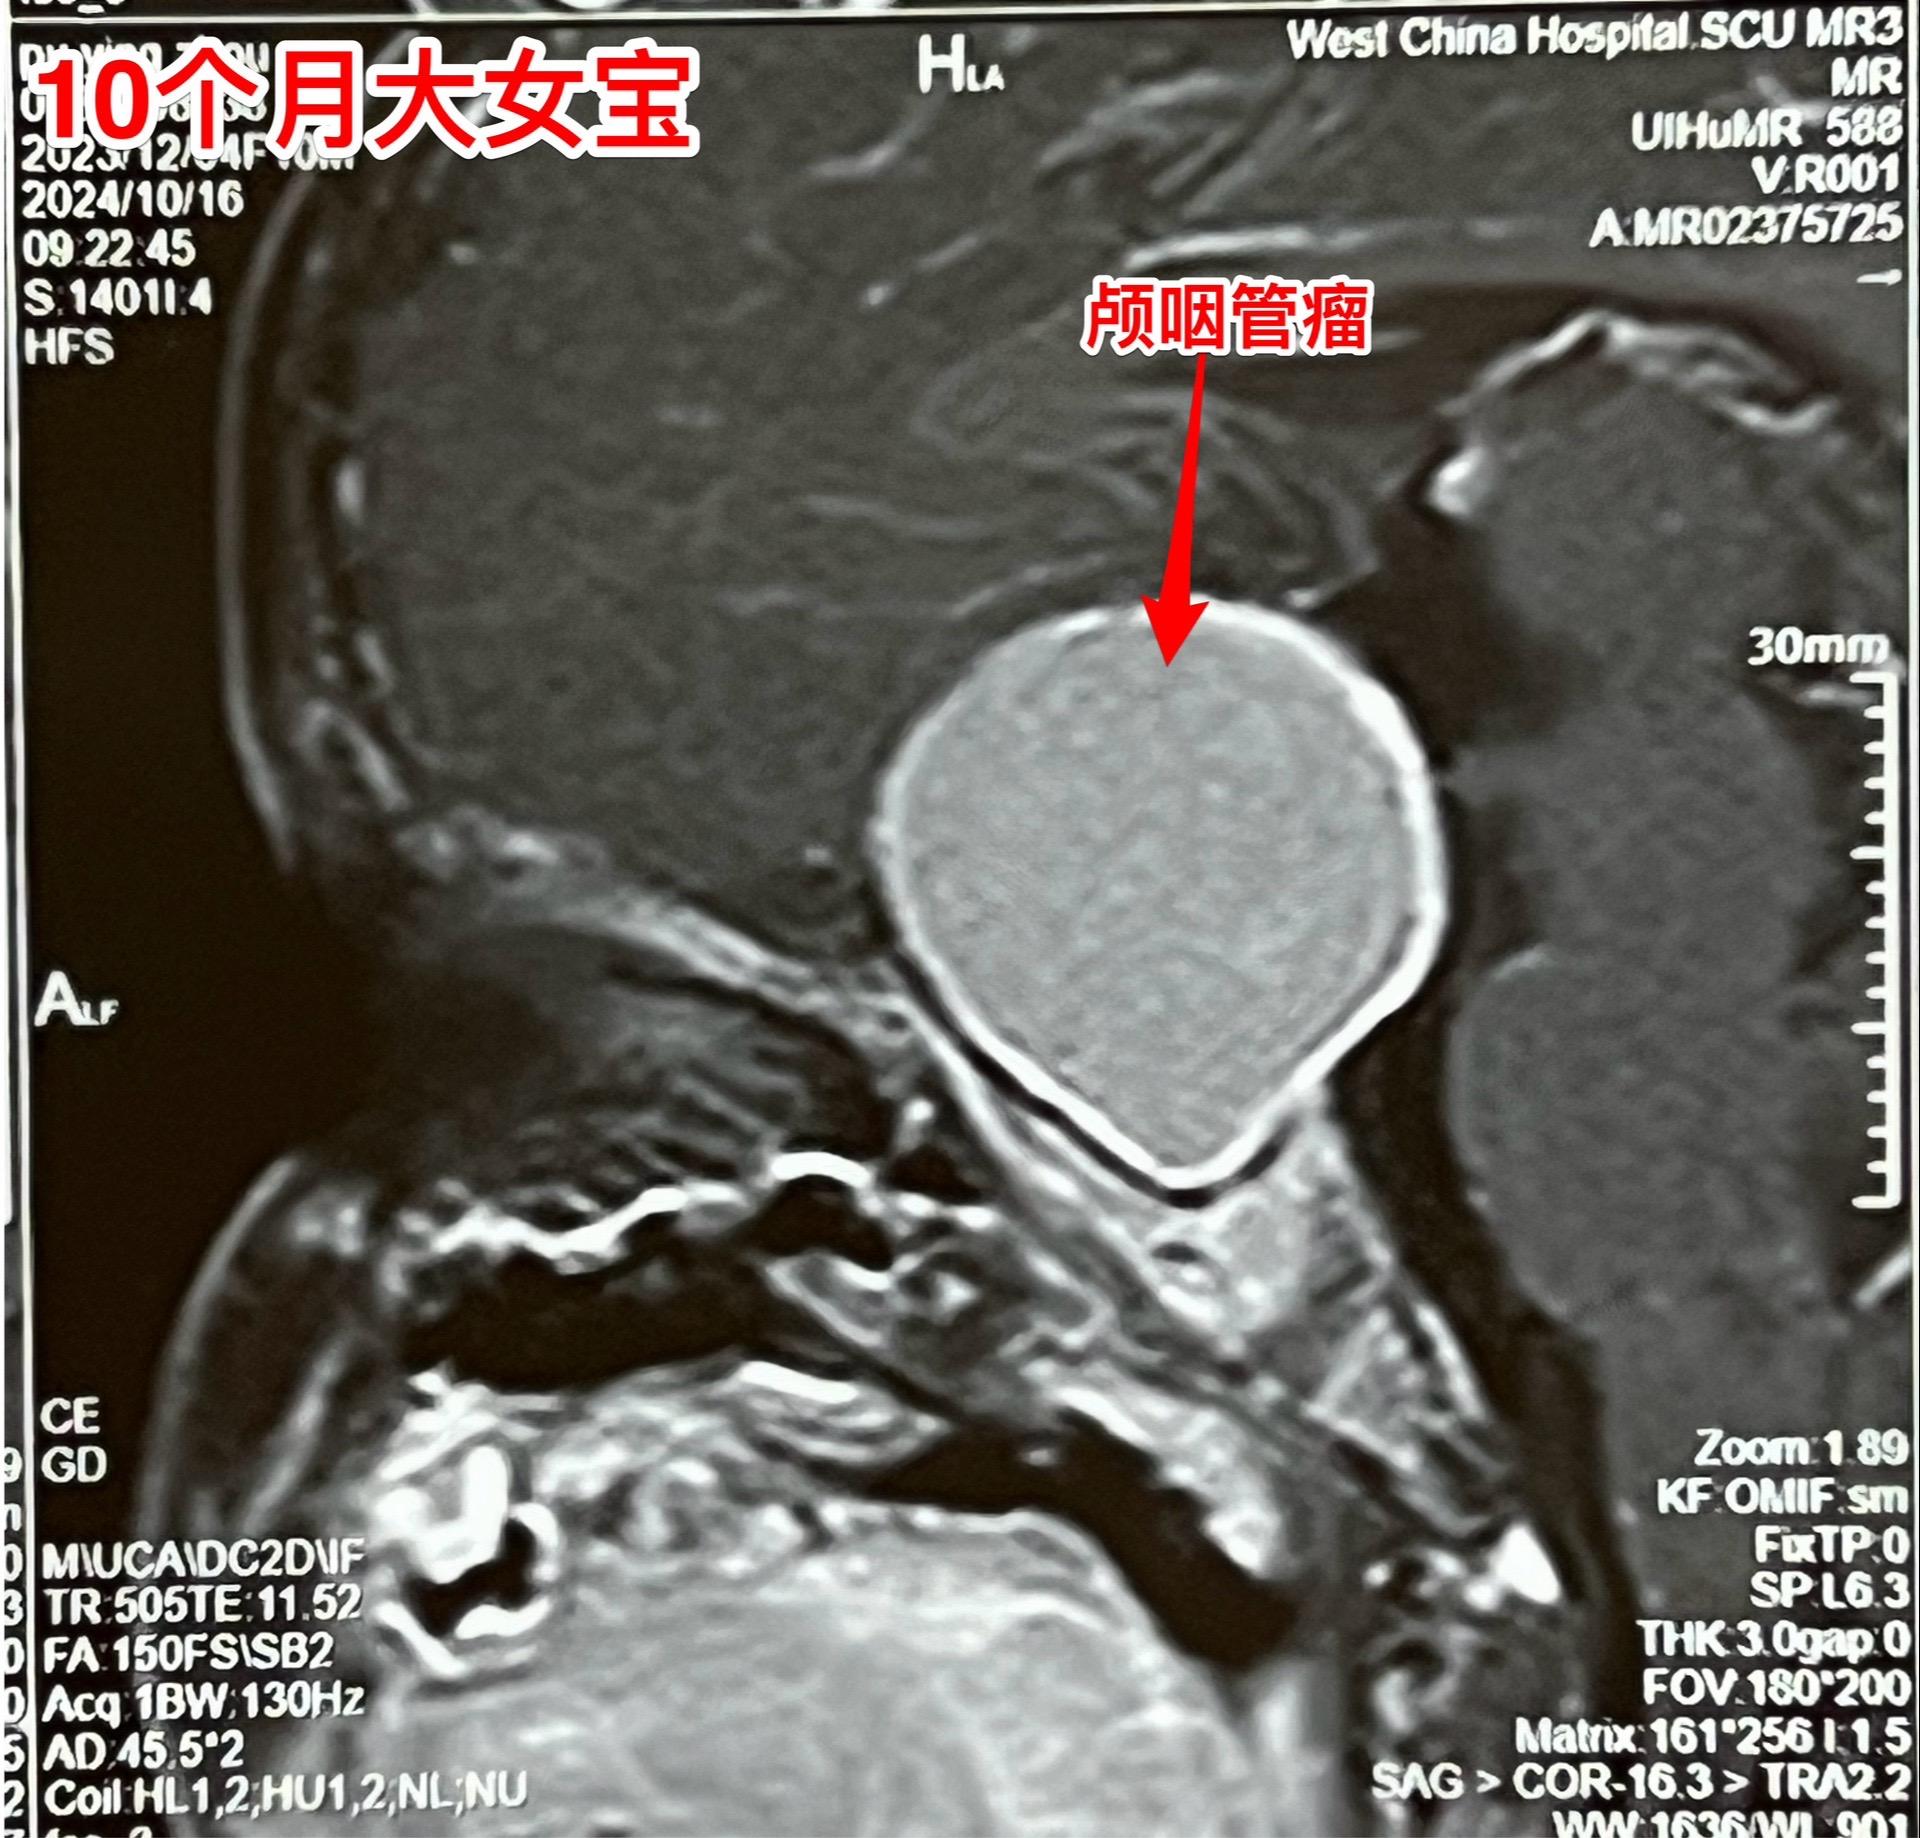

10个月大的宝宝视力下降能不能被家长发现。可以肯定,10个月大的宝宝,无论他有多高的语言天赋,也不会表达视力下降! 所以,对于还不能说话的小宝宝,家长对眼睛的观察就要时时细心才行。 细心的观察一定能发现视力下降的蛛丝马迹! 在两个月前,家长就发现这个成都的女宝眼睛似乎不能追随物体或人物而转动!到眼科去检查,作了磁共振就发现了脑部肿瘤,见图。再结合CT就可以确诊颅咽管瘤了。10.28来住院,住院的时候小朋友的双侧瞳孔对光反应消失了,也就是说已经双目失明了!